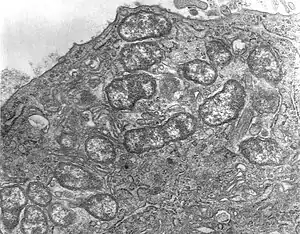

Orientia tsutsugamushi initially attacks the myelocytes in the area of inoculation, and then the endothelial cells lining the vasculature. In the blood circulation, it targets phagocytes such as dendritic cells and macrophages in all organs as the secondary targets. The parasite first attaches itself to the target cells using surface proteoglycans present on the host cell and bacterial surface proteins such as type specific protein 56 or type specific antigen, TSA56 and surface cell antigens ScaA and ScaC, which are membrane transporter proteins.[18][19]

These proteins interact with the host fibronectin to induce phagocytosis (the process of ingesting the bacterium). The ability to actually enter the host cell depends on integrin-mediated signaling and reorganisation of the actin cytoskeleton.[20]